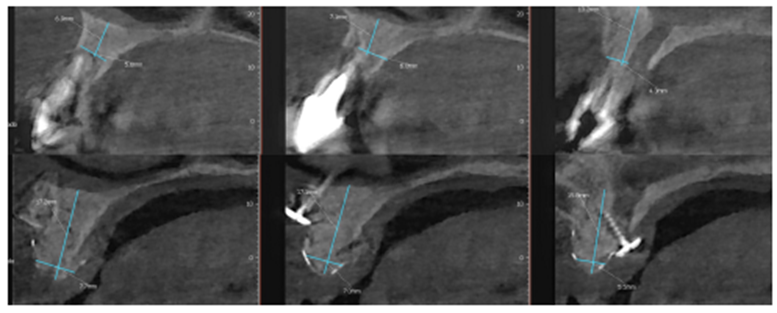

Paciente RV, do sexo masculino de 52 anos, compareceu a nossa clínica com queixa estética e funcional dos dentes incisivos centrais superiores. No exame clínico observou-se doença periodontal severa com presença de bolsa periodontal e perda óssea marginal maior do que 7 mm (Figura 1). Foi realizado em nossa escola (Beo – Ensino Odontológico Avançado) uma tomografia computadorizada para melhor planejamento cirúrgico do caso, onde confirmamos a necessidade de regeneração óssea guiada com membrana Cytoplast com reforço de titânio, devido à perda óssea vertical maior do que 7 mm (Figura 2). Após definição do planejamento cirúrgico, foi realizado a exodontia dos incisivos centrais superiores, limpeza cirúrgica da região e osteotomia periférica para melhor preparo do leito receptor do material de enxertia de lenta reabsorção Bio-Oss (Geistlich) e da membrana Cytoplast com reforço de titânio 30 mm X 40 mm (Figuras 3,4 e 5). Após estabilização da membrana, foi realizado a sutura com fio do tipo Cytoplast 3.0 mm devido a sua alta plasticidade, diminuindo o risco de deiscência de sutura (Figura 6).

Após oito meses, foi realizada nova tomografia para análise do ganho ósseo vertical, assim como o planejamento dos implantes do tipo Cone Morse Maestro – Implacil De Bortoli (Figura 7). Foram planejados e realizados dois implantes 3.5 X 11 mm Cone Morse Maestro após remoção da membrana Cytoplast, devido ao ótimo ganho ósseo vertical, evidenciando sucesso da técnica de regeneração óssea guiada (Figuras 8, 9 e 10). Após a espera de apenas três meses devido a qualidade do implante e suas câmaras de cicatrização, o que possibilita uma osseointegração precoce, foram realizadas duas metalocerâmicas parafusadas sobre pilares Ideale reto, da Implacil De Bortoli, devido ao ótimo posicionamento tridimensional (Figuras 11 e 12).